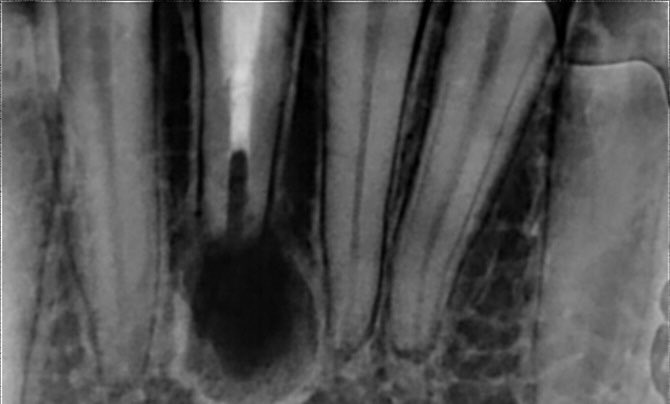

طبيب مقيم في علاج الجذور و عصب الأسنان 🦷 🦷 Endodontic resident at @ksmcmedia 📍Riyadh